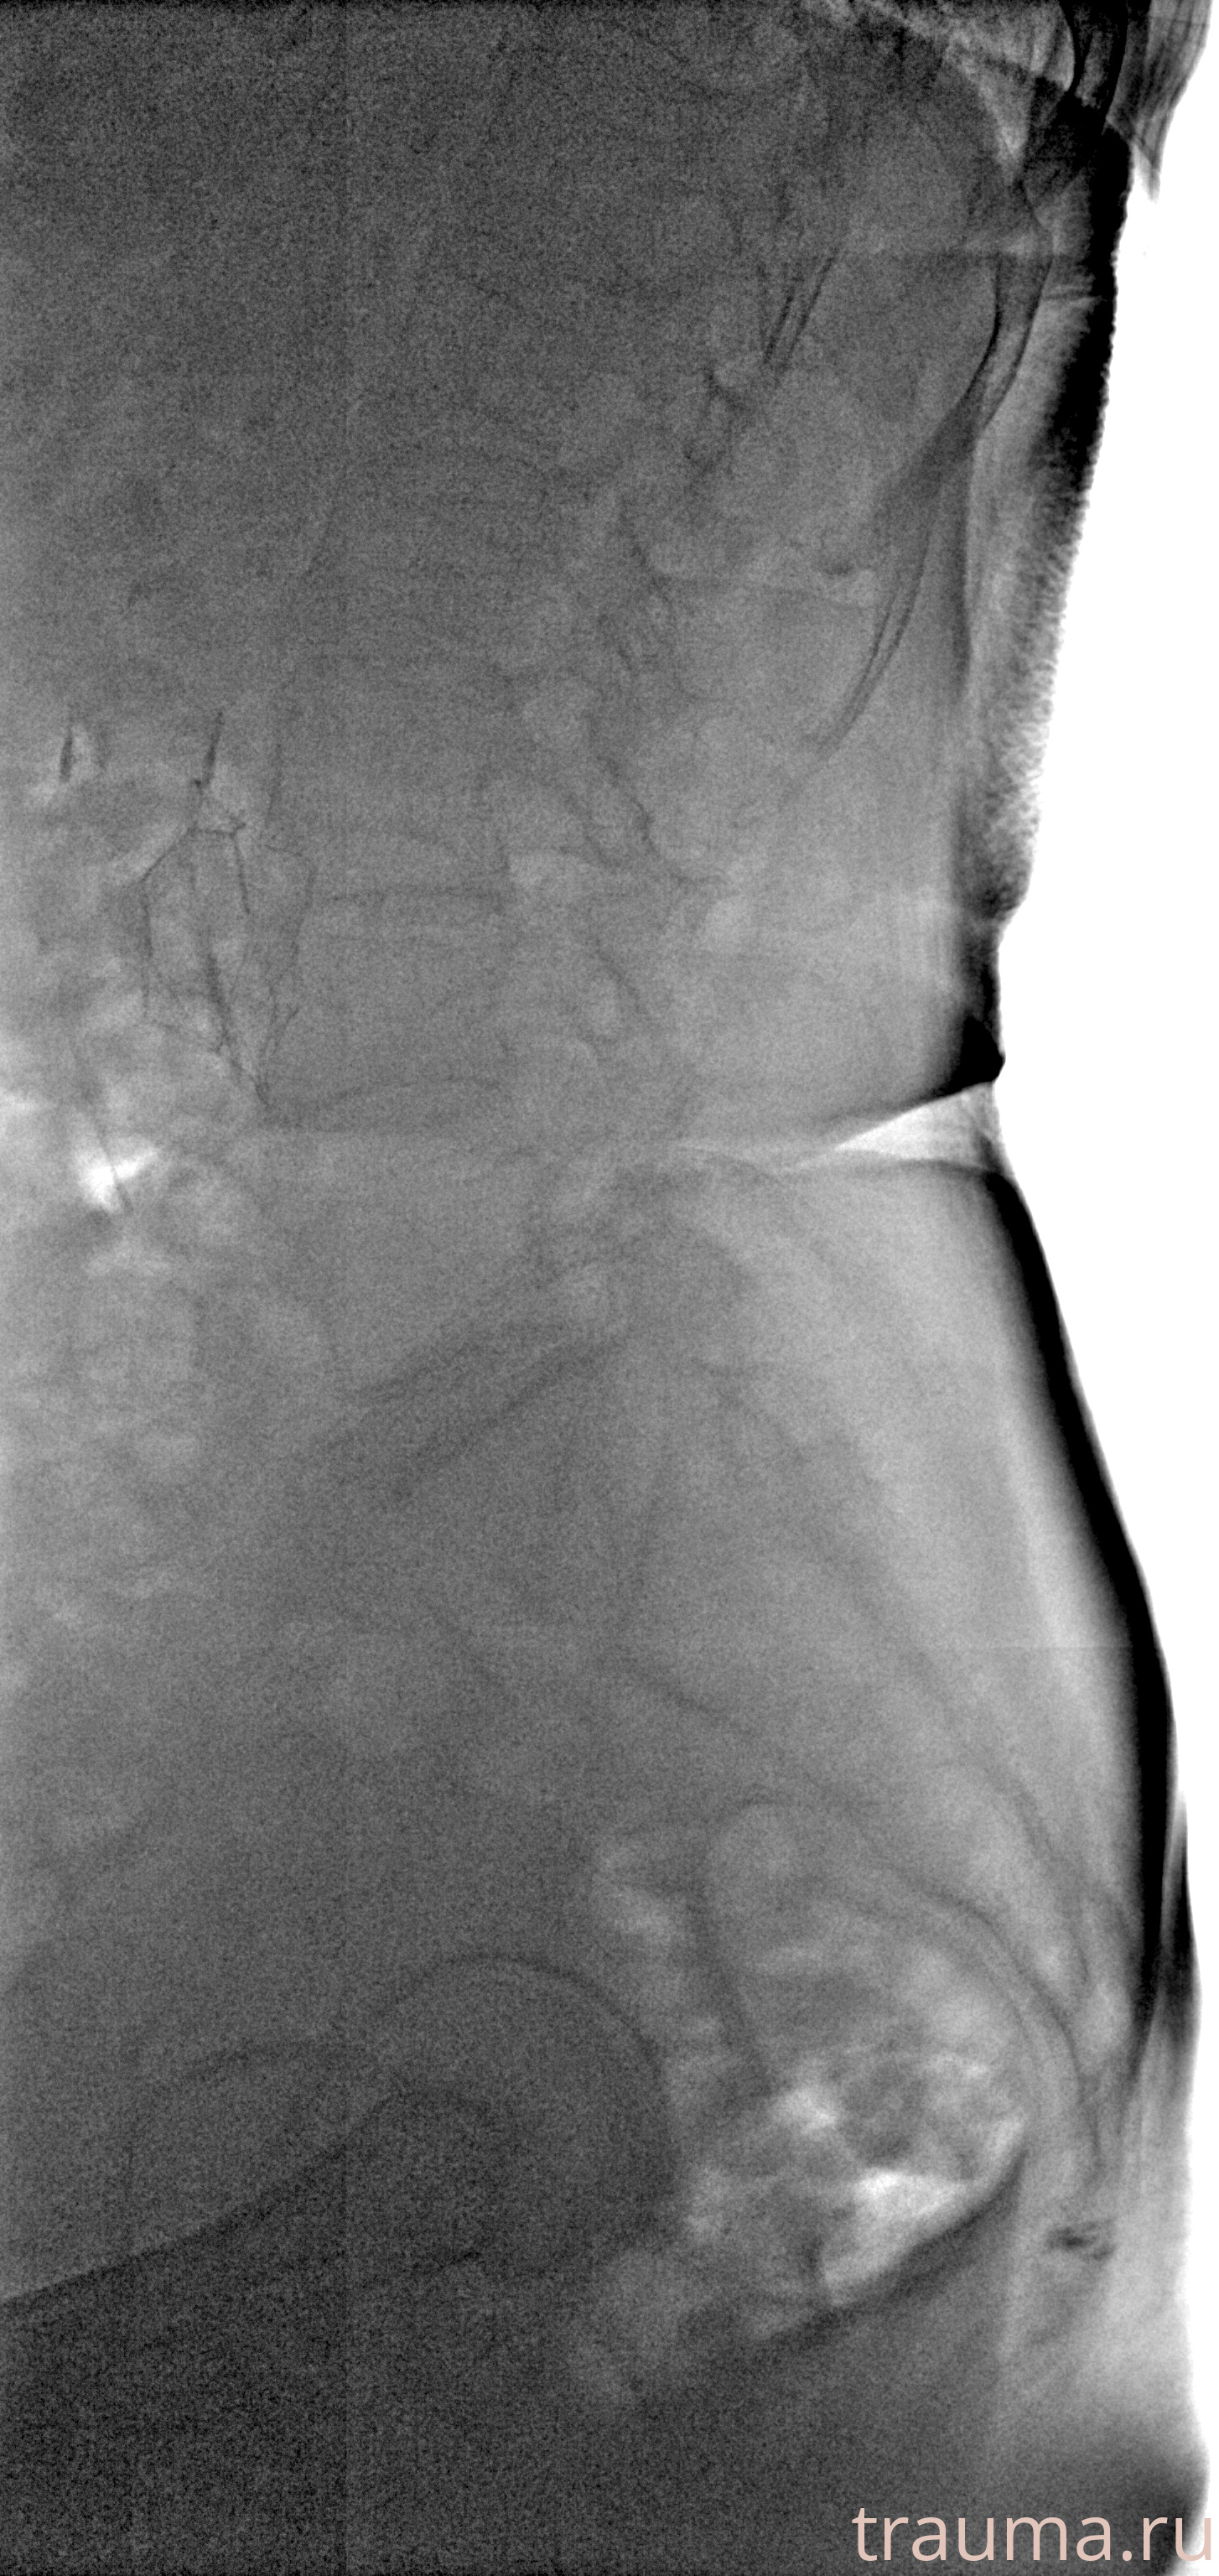

Рентгенограммы

Рентген на дому: по вашему адресу приезжает врач-рентгенолог, травматолог-ортопед с мобильным рентгеновским аппаратом, проводит диагностику травмы или заболевания, делает необходимые рентгенограммы, дает рекомендации по дальнейшему лечению. Получить качественные снимки в домашних условиях возможно благодаря уникальной методике, разработанной МосРентген Центром для института  Склифосовского